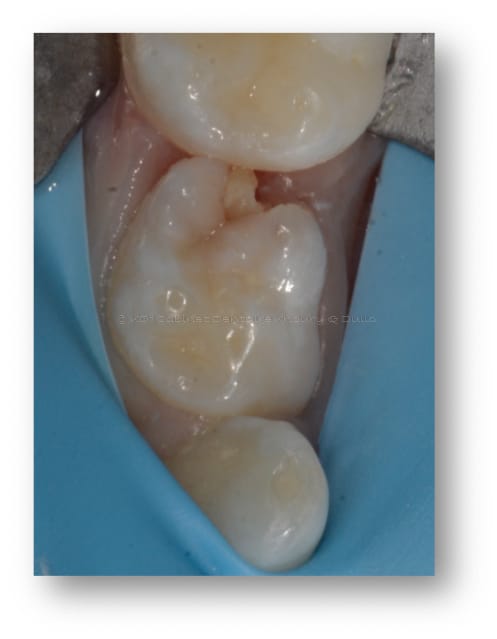

Les différentes étapes pour soigner une carie sur une molaire de lait sont illustrées, depuis l’ouverture de la cavité carieuse, le nettoyage du tissu malade et la restauration de la dent avec du composite.

Caries dentaires affectant deux molaires de lait